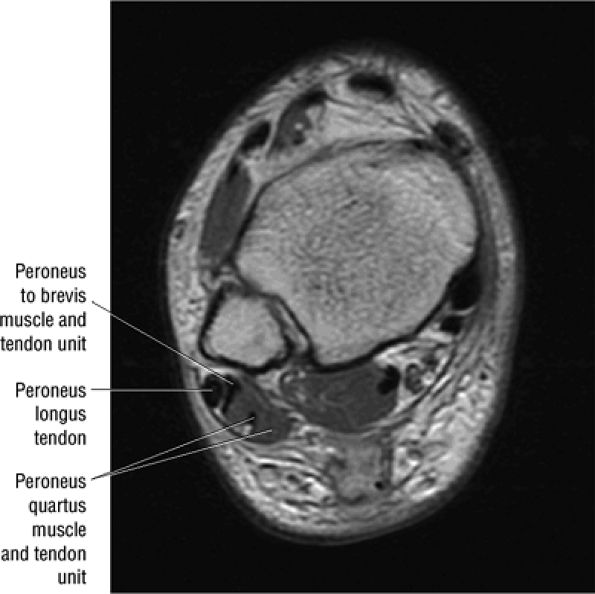

The peroneus quartus muscle is present in 13% to 22% of individuals (Fig. 5.88). This anatomic variant originates from the peroneus brevis muscle and inserts onto the peroneal tubercle of the calcaneus.21

FIGURE 5.88 ● The peroneus quartus (PQ) originates from the distal third of the lower leg, including the peroneal muscles, and inserts onto the calcaneus at and proximal to the lateral malleolus. The PQ is located medial or posterior to the peroneal tendons.